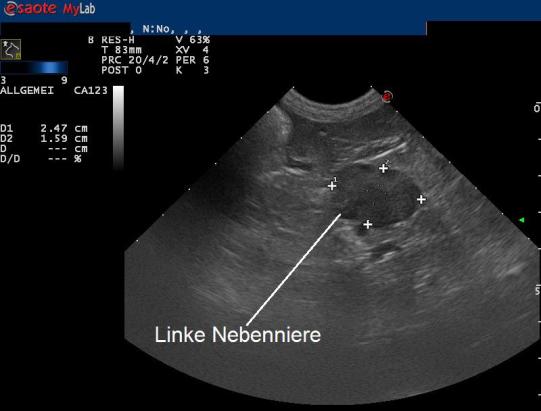

Zur Diagnosesicherung wird ein sogenannter ACTH-Stimulationstest durchgeführt. Hierbei wird der Cortisolwert im Blut vor und nach einer Injektion mit einem Hormon (ACTH), welches die Nebennieren zur Cortisolproduktion anregt, gemessen. Bei Luca steigt der Cortisolwert nach der Injektion extrem an und bestätigt dadurch den Verdacht einer Nebennieren-Überfunktion. Ein weiterer Bluttest sowie ein Ultraschalluntersuch, bei welchem eine vergrösserte linke Nebennieren gefunden wird, komplettieren die Diagnose eines adrenalen (nebennierenbedingten) Cushing-Syndromes.

Zu einer Nebennierenüberfunktion kann es einerseits kommen, wenn sich in einer Nebenniere ein hormonproduzierender Tumor entwickelt (adrenaler Cushing's, ca 15% der Fälle). Typisch ist bei diesen Hunden, dass eine Nebenniere deutlich vergrössert und die andere Nebenniere eher klein ist. Etwa die Hälfte dieser Nebennierentumoren bilden Ableger (Metastasen). In ca 85% der Hunde mit Nebennierenüberfunktion entwickelt sich ein Tumor in der Hirnanhangsdrüse, welcher eine Vergrösserung beider Nebennieren gleichzeitig bewirkt (hypophysärer Cushing's). Zur Differenzierung der beiden Formen kann neben einer Blutuntersuchung auch ein Bauchultraschall oder idealerweise eine Hirnuntersuchung mittels Computertomographie oder Magnetresonanztomographie durchgeführt werden.